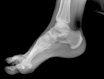

POSICION 1 : PIE AP (DORSOPLANTAR)

Paciente en decubito supino,la rodilla flexionada y con la planta del pie sobre el cassete radiografico.El haz de rayos se dirige verticalmente a la base del primer metatarsiano.

CONSIDERACIONES MEDICAS Posicion 1 : PIE AP

Radiografía en la que se debe tomar en cuenta la totalidad de los elementos, los óseos así como las partes blandas , por lo que es importante recalcar que sean observados , parte del tarso los metatarsianos y sobre todo la orientación de falanges, no es imprescindible el desplegar los sesamoideos ya que estos serán mejor apreciados en enfoques oblicuos y perfiles .También en este enfoque es importante apreciar la congruencia articular del tarso y de los metatarsianos con las falanges , la mesura de los ángulos interdigitales y de las falanges entre si son muy importantes en ortopedia.

Nota jamás conformarse con solo este enfoque , siempre deberá estar acompañado de un perfil , y si es necesario una oblicua . Dr.Aramayo